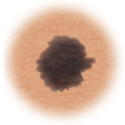

Melanoma

Skin cancer showing more than one color.

Color

When the color of the mole varies throughout